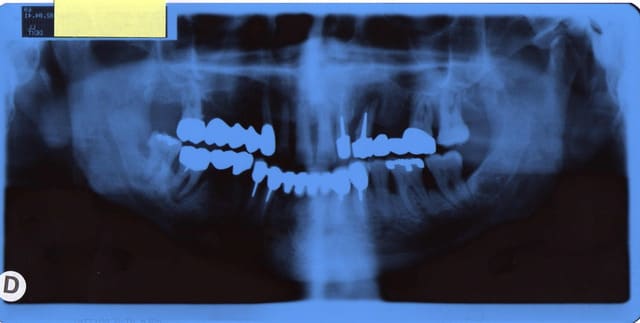

P.S: désolé pour la mauvaise qualité des pano

Opt1lag12 eweogs - Eugenol

D'après moi, un bilan long cône est indispensable.

Un scanner aussi, pour prévoir le comblement.